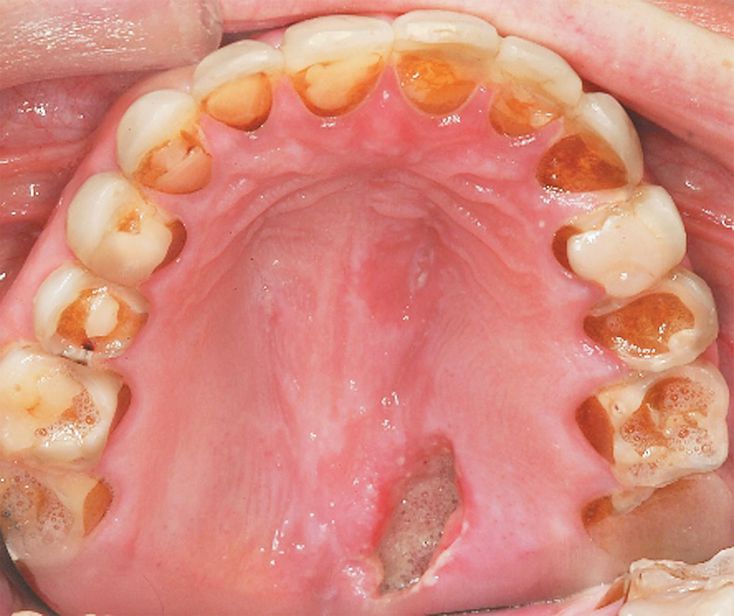

A 27-year-old woman presented with fatigue and a 4-day history of a painful sore in her mouth. Physical examination revealed a body-mass index (the weight in kilograms divided by the square of the height in meters) of 17.2, a deep ulcer of the posterior palate, severe tooth erosion with lingual decay, and swollen parotid glands. Laboratory studies revealed a serum potassium level of 2.6 mmol per liter and a bicarbonate level of 34 mmol per liter. The patient reported binge eating and self-induced vomiting several times daily. Given the binge-eating and purging behaviors, as well as hypokalemic metabolic alkalosis, palatal ulceration, and severe tooth erosion and decay, she was given a diagnosis of bulimia nervosa. Persons with eating disorders are likely to present in a primary care setting, and health care providers are in a unique position to identify the coexisting conditions and provide early detection, treatment, and appropriate referrals. This patient was hydrated with intravenous saline and was seen by the psychiatry and dentistry services. At the 1-year follow-up, the patient reported normal eating habits and her physical examination and results of laboratory tests were normal.